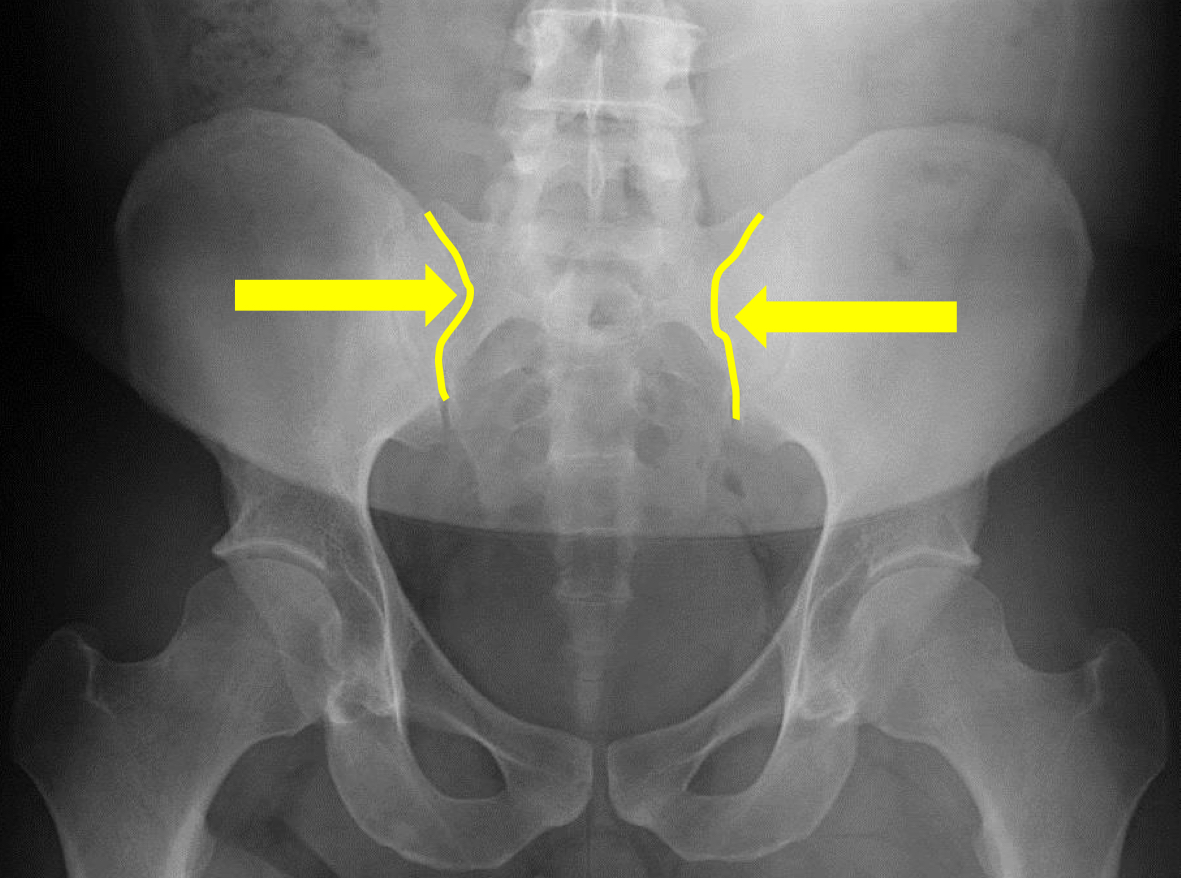

What view is this?

AP (Anterior to Posterior) LumboPelvic

What is this?

Femur Heads

What is this?

Superior Iliac Crests

What is this?

Lateral Iliac Crests

What is this?

Ischial Tuberosites

What is this?

Obturator Foramen

What is this?

S2 Tubercle

What is this?

Pubic Symphysis

What is this?

Sacral Groove

What is this?

Lateral aspect of sacrum

What is this?

Medial Aspect of Ilium